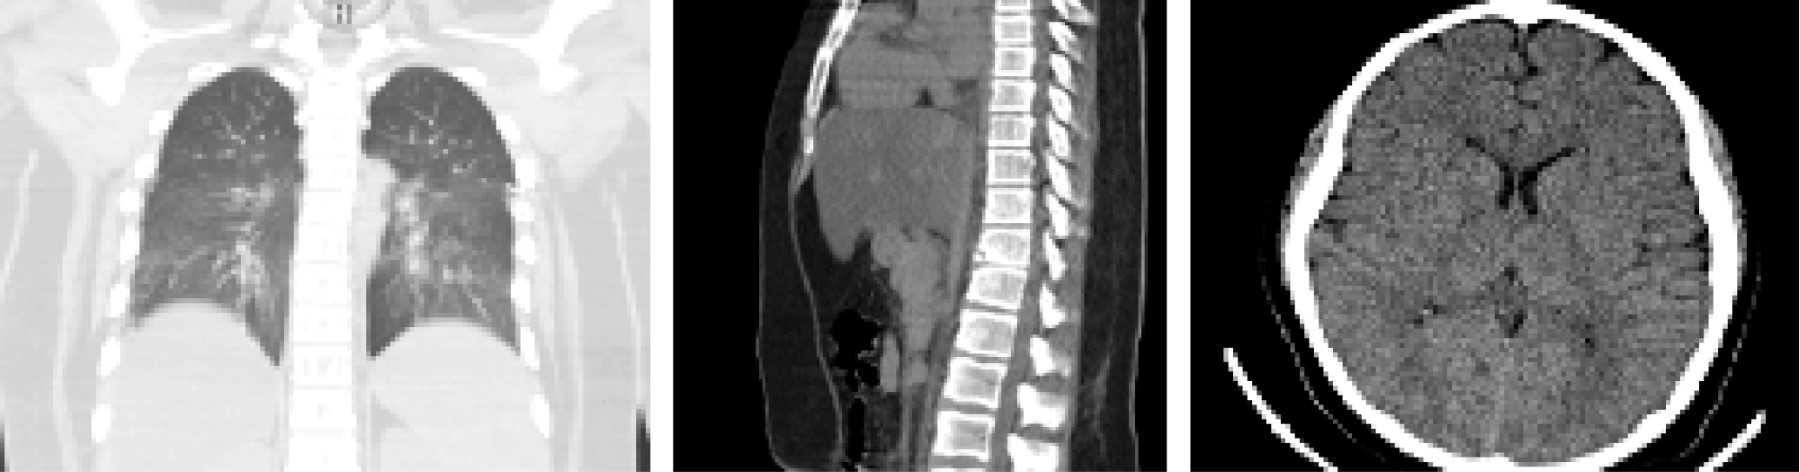

Se solicita panel molecular meníngeo con resultado negativo y se solicita estudio de imagen por tomografía como se muestra en la Figura 1.

Figura 1